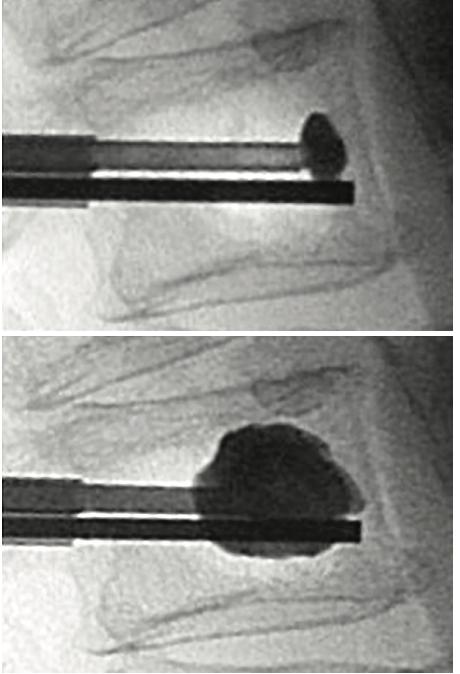

5 Balloondeployment: ballooncathetersareinsertedthrough theaccesscannulasandsubsequentlydeployed Again, imagesaretakentoconfirmcorrectballoonplacement

Confirmationofplacement:Onceaccessthroughthe pedicleshasbeenachieved,ahanddrillisusedocreatea channelforthesubsequentballoons APimageistakennow toconfirmplacement. Thisisrepeatedontheoppositeside.

6 Ballooninflationandcementinjection: Balloontampsare advancedbilaterally Eachballoontamp,attachedtoa lockingsyringewithadigitalmanometer,istheninflatedwith iodinatedcontrast APandlateralimagesareobtained duringinflationtoguaranteesafeandproperepansionand fracturereduction Onceexpansionisadequatelyperformed, balloonsaredeflatedand injectionofcementiscarriedout (cementcannulaisintroducedintoaccesscannulaforthis step). Enoughcementtofillvoidcreatedbyballoonsshould beinjected

Completionofprocedure:cementcannularemovedand styletneedleintroducedintoworkingcannula Oncecement hassecured,cannulais removedunderconstantimagingto detectanyposteriormigrationofcement

Figure14:IllustrationofKyphoplastyprocedure A)lateralfluoroscopicimagesofbonecementcannula insertion(topleft),ballooninflation(topright),bone cementevenlydistributedinvertebralbody(bottomleft), APviewofbilateralballoonkyphoplasty(bottomright) B)simplifiedillustrationofprocedure;needleadvanced intovertebralbody(topleft),ballooninflated(topright), balloondeflatedandcementinjected(bottomleft), cementin-situ(bottomright)